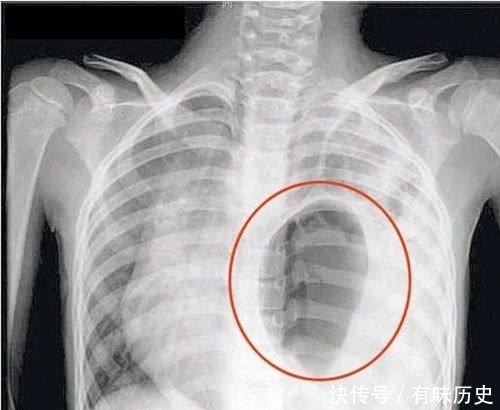

食管裂孔疝指的是人体内脏器官(主要是胃)通过膈食管裂空进入人体的胸腔所引发的疾病。在膈疝中这种病症最为常见,属于消化内科疾病,食管裂孔疝的病发不分年龄,可以是任何人群。病发原因也不是一种,有些人是先天性的食管发育不足,还有的是因为肌肉萎缩又或者是后天的腹腔压力过大导致以及受到创伤等。

食管裂孔疝有不同的临床表现。首先是胃食管反流症状,即胸骨后或者剑突下有烧灼感、胃内容物上反感、上腹疼痛感等。并且疼痛感还可能放射到背部、肩部以及颈部等身体部位。其次是并发症,其中包括裂孔疝的出血现象,严重的可致贫血,并且疝入的胃和肠如果发生溃疡会造成呕血和黑便的现象,还有吞咽食物困难、疼痛以及呕吐现象。除上述以外,裂孔疝病人如果突然感觉上腹有剧烈的疼痛感并伴随呕吐,完全不能吞咽或者出现大出血情况,则提示发生急性嵌顿。